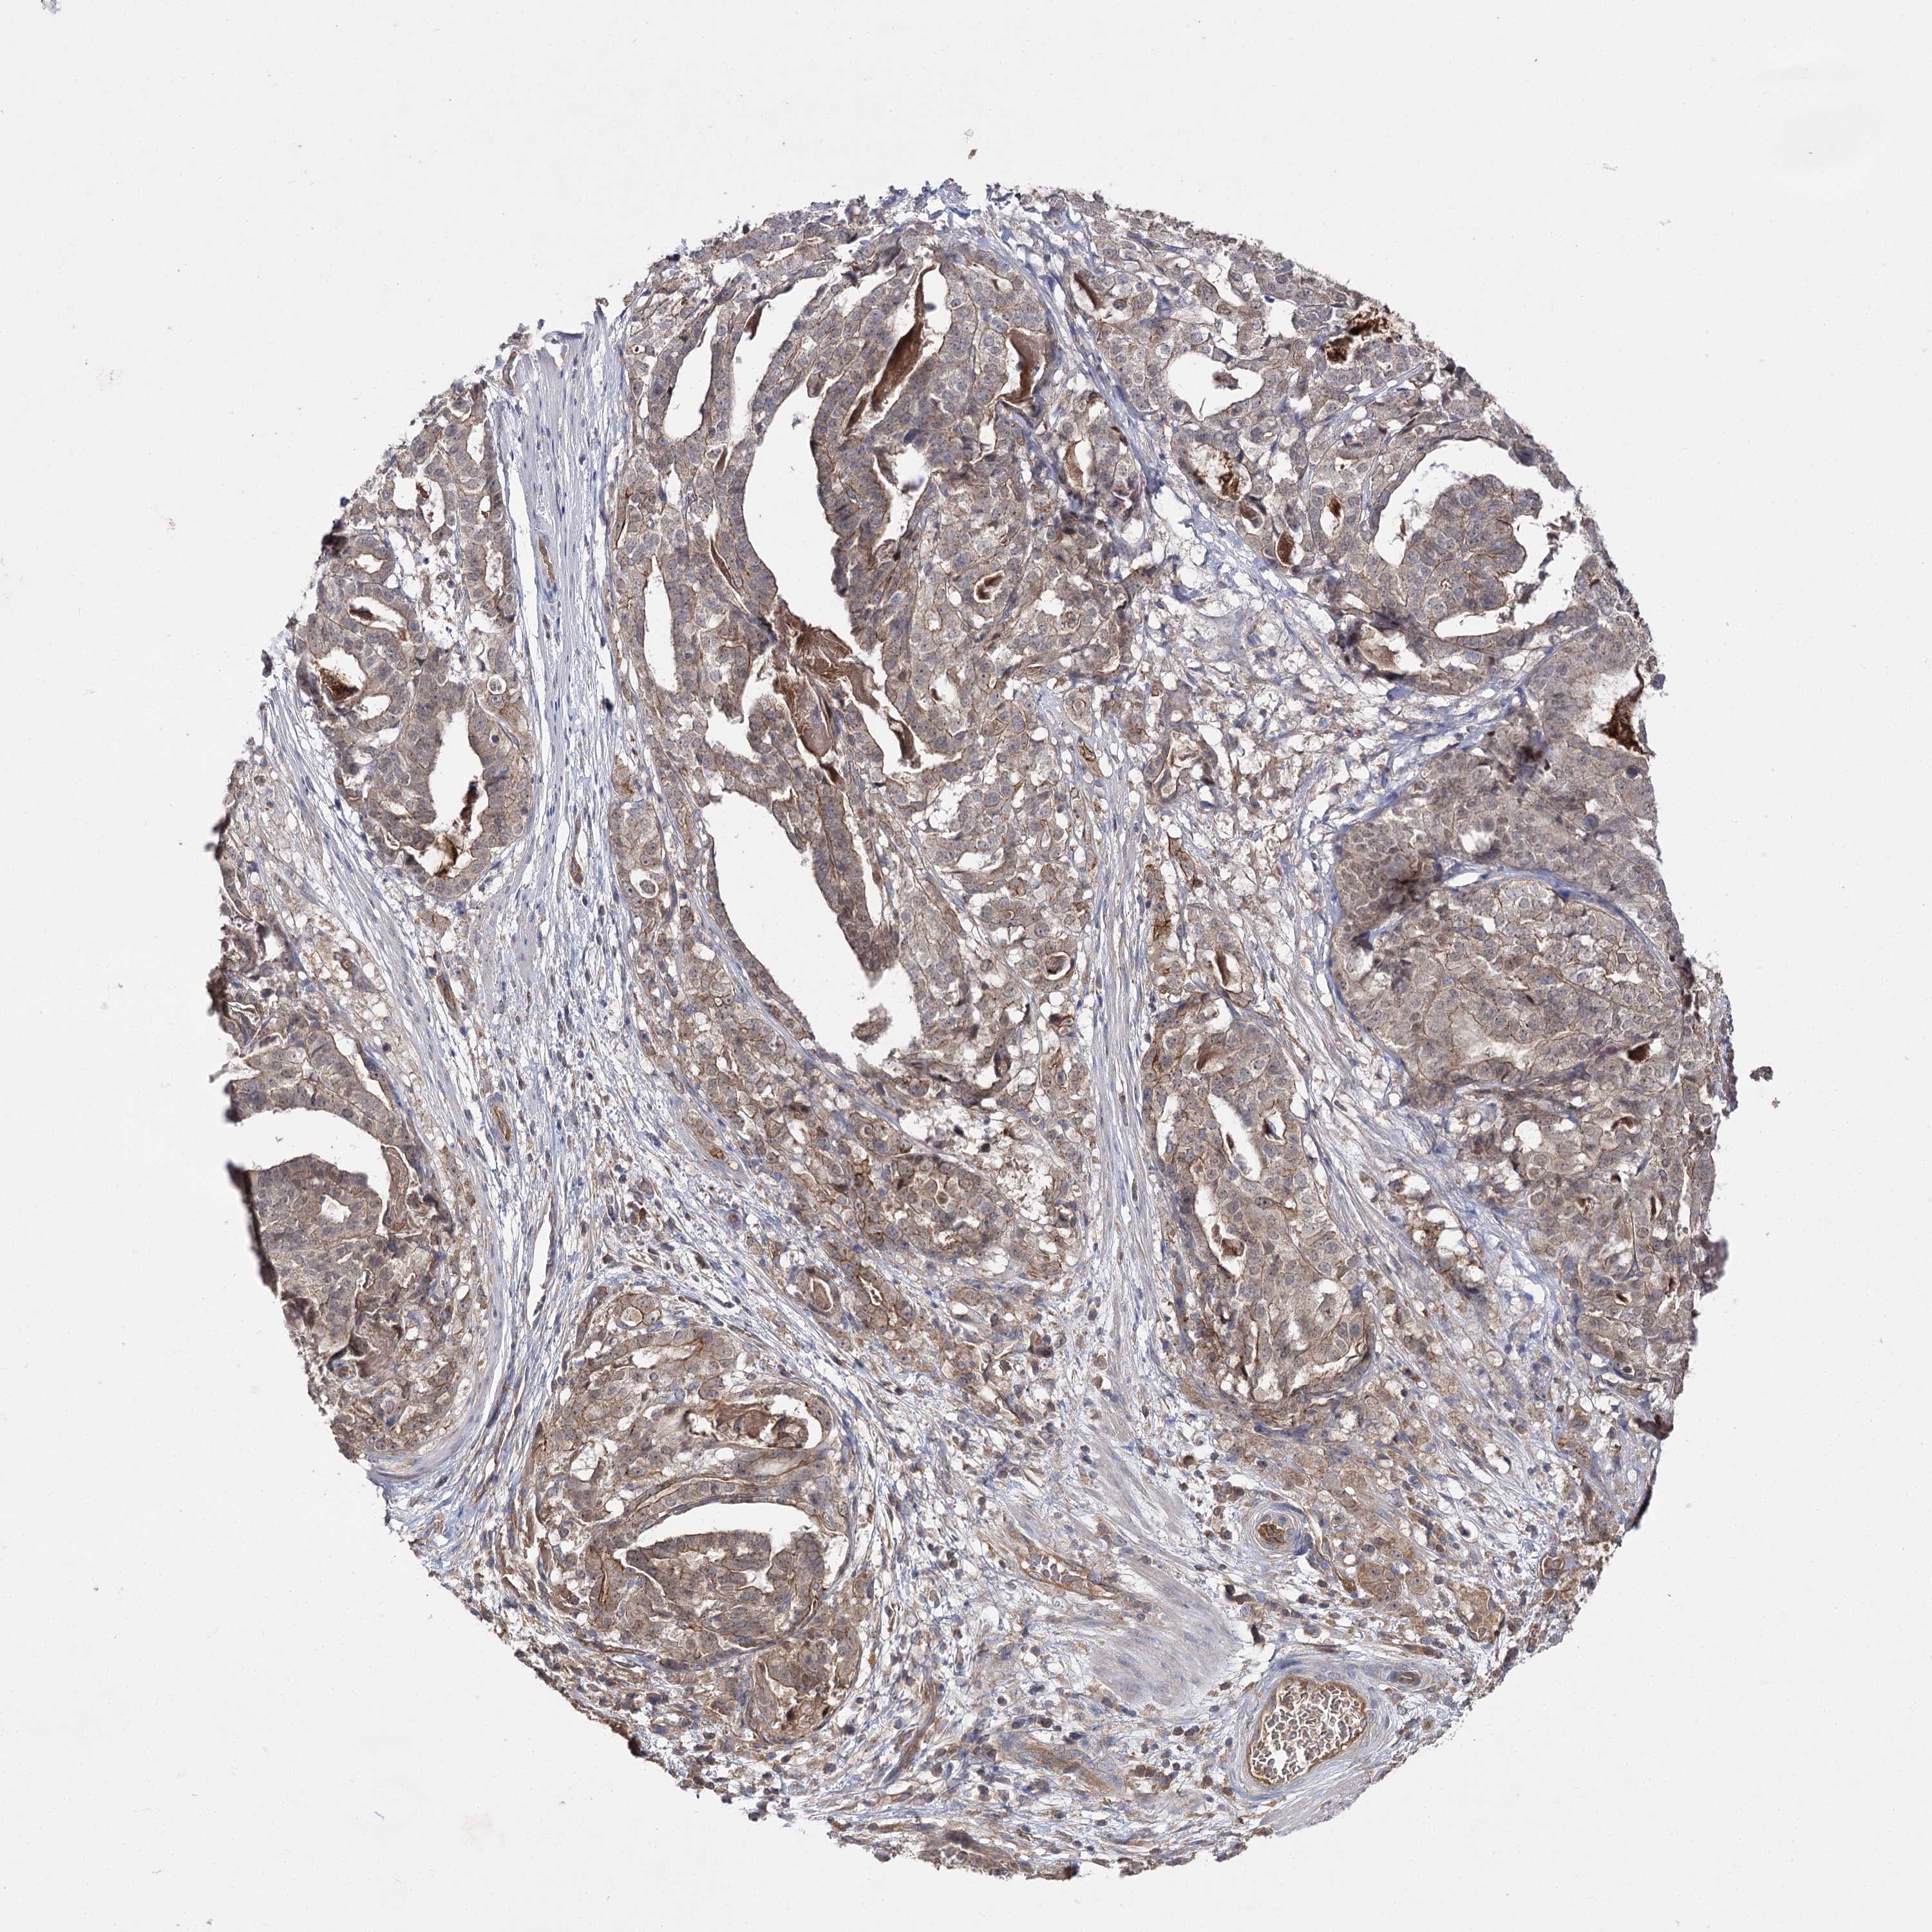

STOMACH CANCER - Protein expressioni

A mouse-over function shows sample information and annotation data. Click on an image to view it in a full screen mode. Samples can be filtered based on level of antibody staining by selecting one or several of the following categories: high, medium, low and not detected. The assay and annotation is described here.

Note that samples used for immunohistochemistry by the Human Protein Atlas do not correspond to samples in the TCGA dataset.

Antibody stainingi

Antibody staining in the annotated cell types in the current human tissue is reported as not detected, low, medium, or high, based on conventional immunohistochemistry profiling in selected tissues. This score is based on the combination of the staining intensity and fraction of stained cells.

Each image is clickable and will lead to virtual microscopy that enables deeper exploration of all samples and also displays staining intensity scores, fraction scores and subcellular localization as well as patient and tissue information for each sample.

Antibody HPA038337

Antibody CAB010421

Antibody CAB018545

Staining

High

Medium

Low

Not detected

Intensity

Strong

Moderate

Weak

Negative

Quantity

>75%

75%-25%

<25%

None

Location

Nuclear

Cytoplasmic/membranous

Cytoplasmic/membranous,nuclear

Adenocarcinoma, NOS